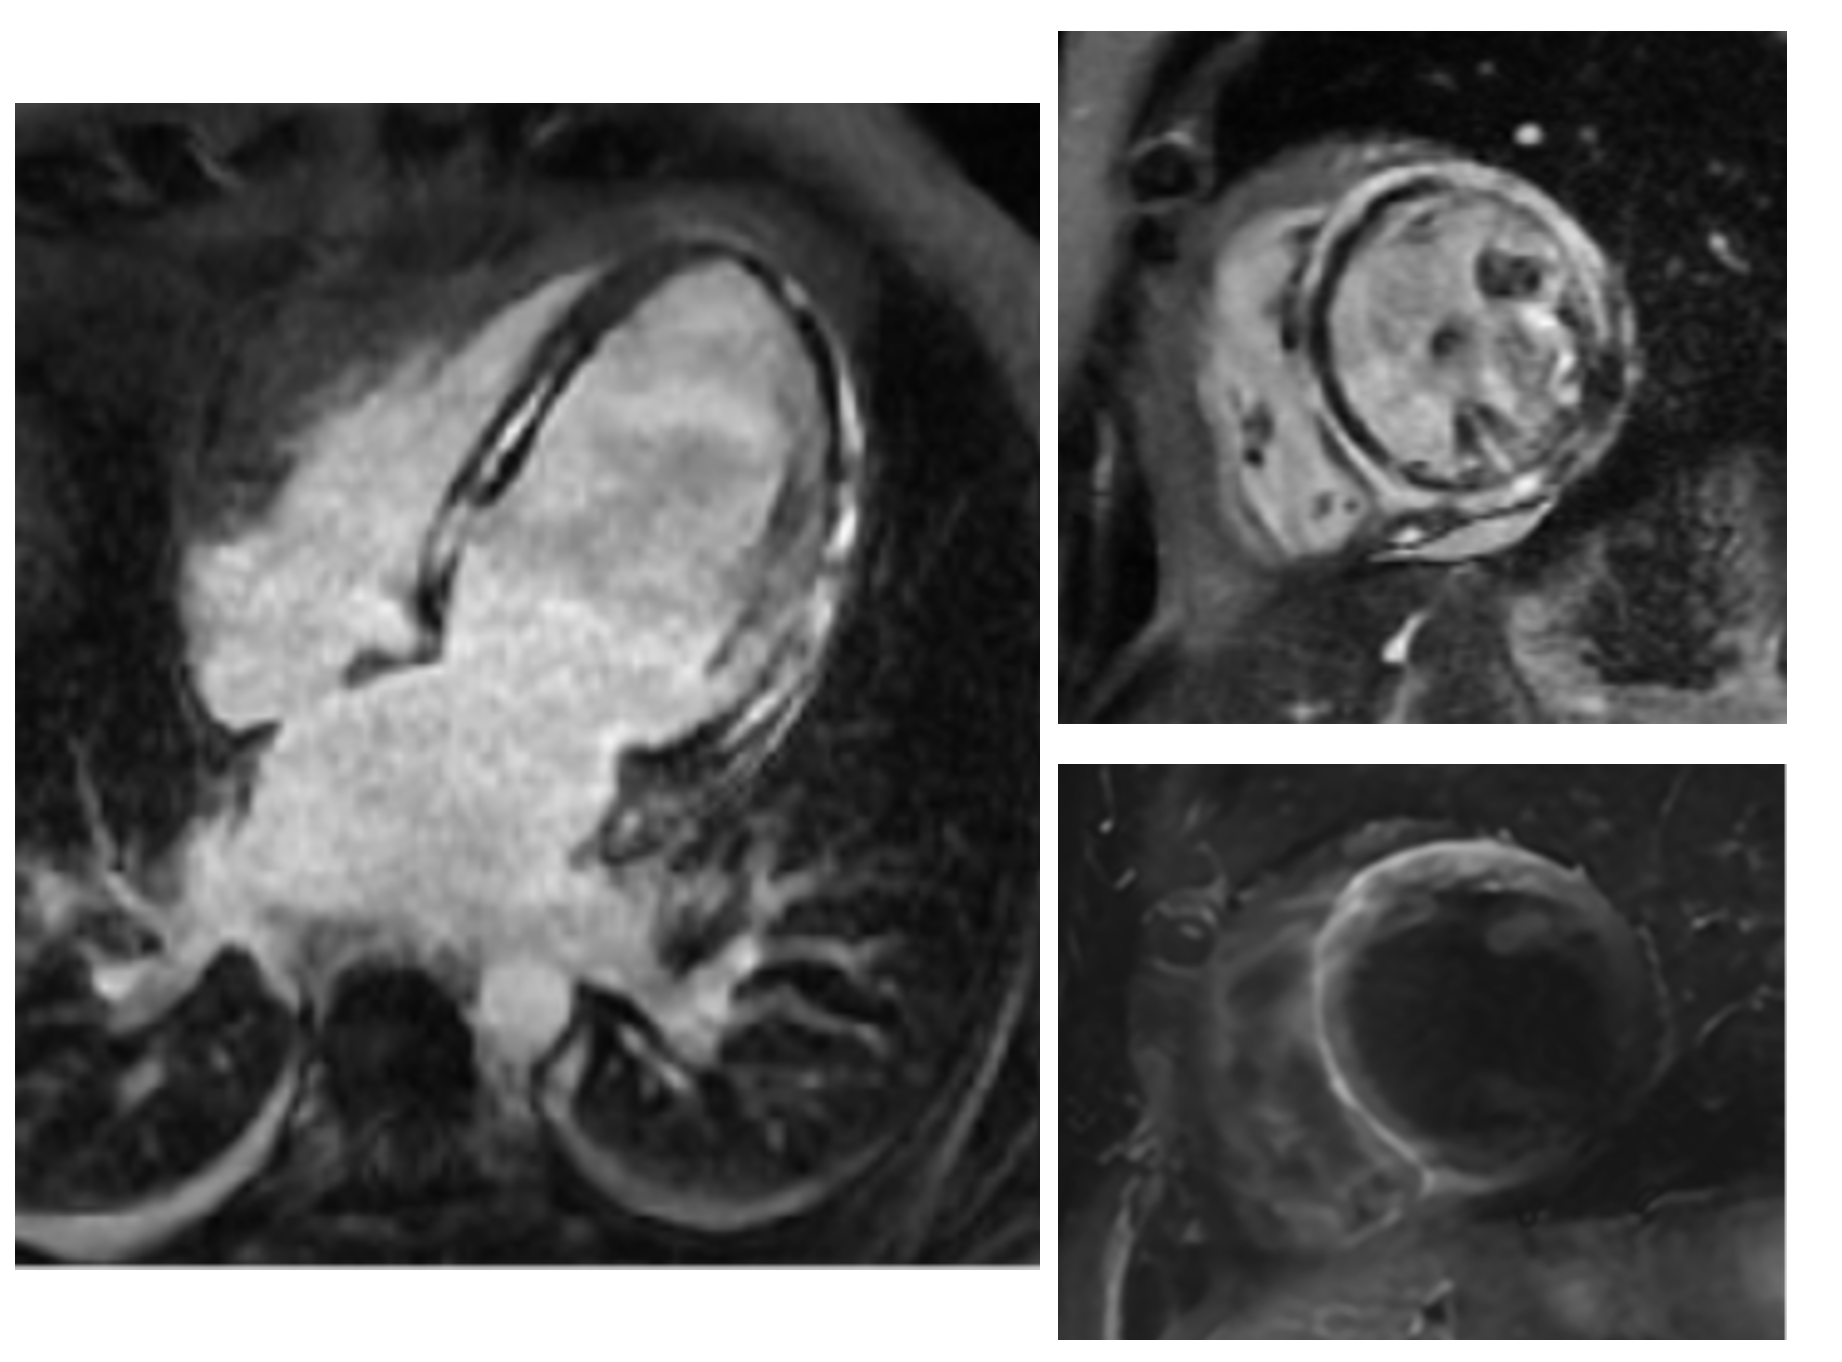

Second CMR SAX view showing LV and RV thrombi, with T2 image with corersponding edema